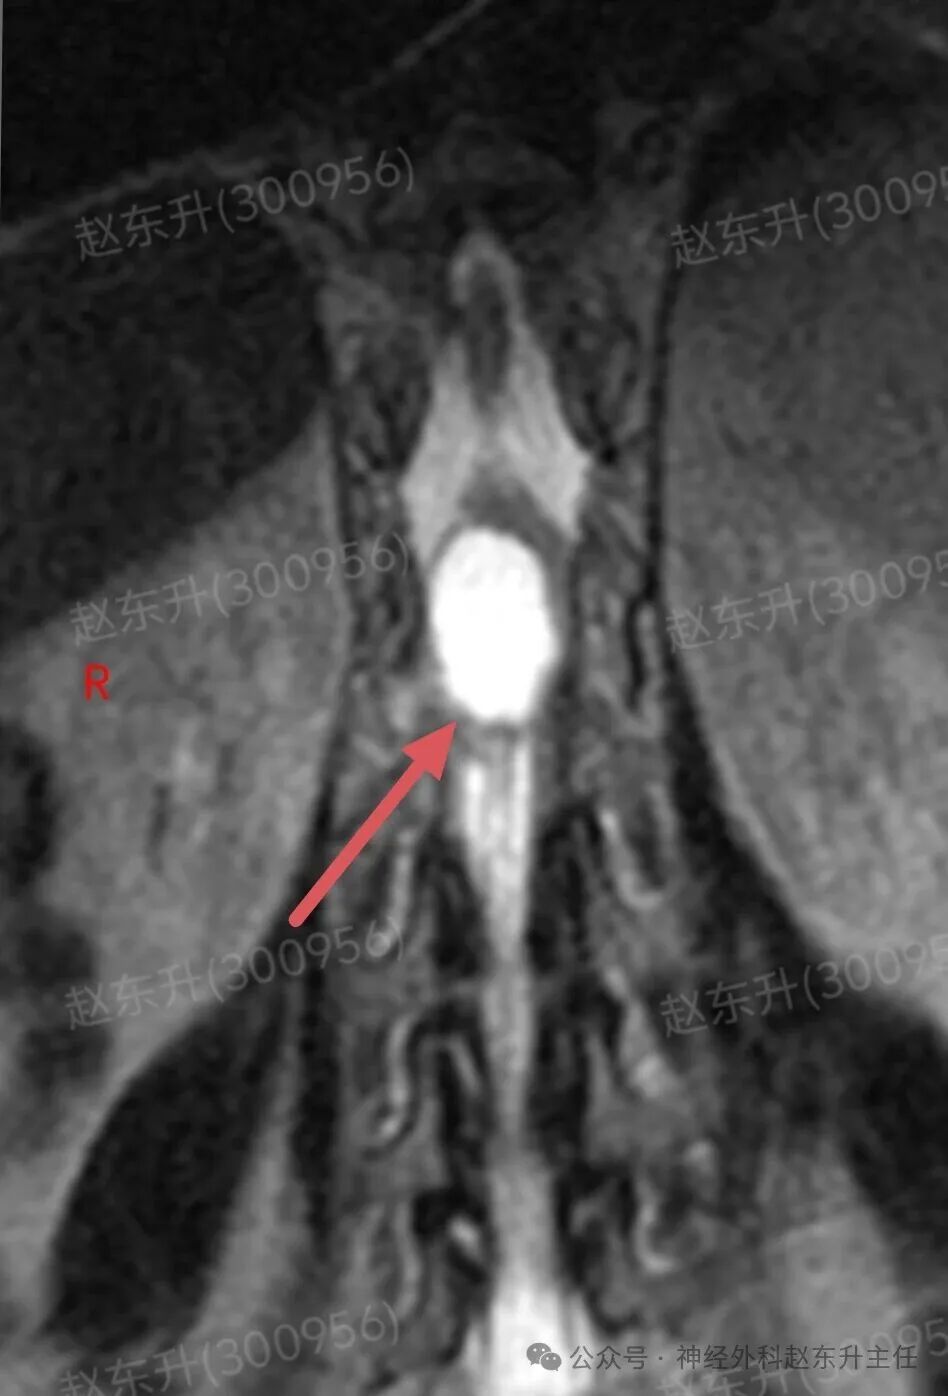

上周门诊来了一位58岁女性,患者因为下肢和腰背部顽固性疼痛半年,在各大医院就诊曾行针灸按摩,艾灸电疗等治疗没见缓解,而且疼痛评分可以达到8-9分,口服止痛药无效,康复理疗无效。随后查了一下腰椎磁共振,发现胸12腰1节段脊髓内异常信号,随后收入我科。入院之后查肌电图提示下肢和骶神经损伤严重,随后我们在全麻下使用显微镜,并且术中电生理监测下,给予脊髓内肿瘤次全切除,术后病理提示是胶质瘤。术后第2天我们就给他用了经颅磁刺激等神经康复治疗,虽然术后第1天右下肢肌力较术前减退,但经过10天的治疗以后,下肢肌力逐渐恢复,可以下地行走了。术后他还需要进一步的放疗和化疗来抑制肿瘤的生长,预防肿瘤复发。

图片图片图片图片图片图片图片图片切除的肿瘤图片术后病理西安市红会医院神经外科赵东升主任介绍:脊髓内胶质瘤是一种起源于脊髓实质内部的胶质细胞(即神经系统的“支持”细胞)的肿瘤。与脊膜瘤(位于脊髓外)的关键区别在于,它生长在脊髓内部,因此会浸润并破坏正常的脊髓神经组织核心特征:性质:涵盖从低级别良性到高级别恶性的完整谱系,但以低级别为主。位置:完全位于脊髓中央,可累及多个脊髓节段,甚至全长脊髓。特点:肿瘤与正常脊髓组织边界不清(浸润性生长),手术全切极为困难。其生长直接破坏神经传导束,导致严重神经功能障碍。发病率:相对少见,约占所有中枢神经系统胶质瘤的2-4%,但却是儿童最常见的髓内肿瘤。无明显性别差异。与脊膜瘤的关键区别总结

主要类型1.室管膜瘤(约占60%):常见的成人髓内胶质瘤。多为低级别(WHO I级和II级),生长缓慢。常发生于颈段和胸段,常有明确边界,有时可有“假包膜”,是手术全切希望最大的一种。2.星形细胞瘤(约占30%):常见的儿童髓内胶质瘤。从低级别(毛细胞型星形细胞瘤,WHO I级,预后好)到高级别(胶质母细胞瘤,WHO IV级,预后极差)都有。浸润性生长为特点,与正常脊髓几乎无边界,手术全切风险极高。3.其他少见类型:如血管母细胞瘤(常与VHL病相关)、少突胶质细胞瘤等。临床表现(症状)症状因肿瘤生长缓慢而隐匿、渐进性加重,早期易被忽视。典型症状:1.感觉障碍(最早、最常见):l分离性感觉障碍:这是特征性表现。由于肿瘤侵犯脊髓中央的白质前连合,导致痛觉、温觉纤维受损,而触觉、深感觉保留。患者表现为双侧对称性的、节段性的痛温觉减退或消失,而触觉正常l麻木、酸痛、束带感。2.运动障碍:n肿瘤平面以下出现肢体无力、僵硬、肌肉萎缩(尤以手部小肌肉萎缩常见)。n行走困难,步态不稳。3.疼痛:定位不明确的颈背部疼痛,夜间痛可能更明显。4.自主神经功能障碍(晚期):l大小便失禁或困难。l性功能障碍。l皮肤营养障碍(无汗、皮肤干燥等)。诊断增强磁共振(MRI): 是首选和确诊的关键检查。典型表现:可见脊髓呈梭形、偏心性或中心性增粗。肿瘤在T1像呈等或低信号,T2像呈高信号,增强后强化模式多样(可均匀、不均匀或环形强化)。可清晰显示肿瘤范围、有无囊变、脊髓空洞等。CT:价值有限,主要用于评估是否有脊椎骨质改变。治疗治疗远比脊膜瘤复杂,需在多学科团队(神经外科、肿瘤科、放疗科)指导下进行个体化综合治疗手术治疗(首要且核心):l目标:在最大限度保护神经功能的前提下,实现最大安全程度的肿瘤切除。全切是目标,但常因肿瘤边界不清而无法实现。l技术:在术中神经电生理监测(监测运动、感觉传导束功能)的保驾护航下,使用显微外科技术、超声吸引、激光等进行精细操作。功能保护优先于肿瘤全切放射治疗:主要适用于:高级别胶质瘤术后辅助治疗、无法全切的低级别胶质瘤术后残留、肿瘤复发无法再次手术者。化学治疗:l对于高级别(恶性)脊髓胶质瘤,可参照脑胶质瘤方案进行化疗(如替莫唑胺)。l对于部分复发的低级别胶质瘤也可能使用。预后与随访预后差异巨大,高度依赖于肿瘤的病理类型和分级l低级别室管膜瘤:若能实现全切,预后良好,可达到长期无进展生存,甚至临床治愈。复发率低。l低级别星形细胞瘤(如毛细胞型):全切后预后也很好。次全切后也可能长期稳定。l高级别胶质瘤(如胶质母细胞瘤)预后极差,即使积极治疗,也极易在脊髓内播散复发,生存期短。l随访:术后需定期(通常每3-6个月,后逐渐延长)进行增强MRI复查,监测肿瘤是否残留或复发。神经功能康复治疗至关重要赵东升主任简介医学硕士,西安市红会医院北院区神经外科主任医师,从事神经外科近20年。使用独创的“三维一体疗法”成功促醒大量昏迷病人,使上百例脊髓损伤瘫痪患者重新站起来。最早在陕西省开展第一例脊髓电刺激治疗昏迷病人,第一例脊髓电刺激手术治疗截瘫病人,第一例脊髓电刺激手术治疗下肢缺血顽固性疼痛。主编专著3部,参编专著11部,发表学术论文30余篇,荣获国家专利32项(其中四项发明专利),担任多部杂志编委及审稿专家。擅长:1.脑病方面:昏迷促醒,脑肿瘤、脑积水、脑梗死偏瘫、肌张力增高、顽固性癫痫、三叉神经痛、脑干出血、老年痴呆、帕金森、头痛等;2.脊髓病方面:脊髓损伤、脊柱术后疼痛、大小便障碍、脊髓肿瘤、脊髓空洞、小脑扁桃体下疝畸形、脊髓栓系、脊膜膨出、痉挛性截瘫等;3.周围神经疾病方面:糖尿病足、下肢缺血性疼痛、臂丛神经损伤、腓总神经损伤、腕管综合征、肘管综合征、男性功能障碍等门诊时间:北院区:周一全天门诊二楼203A  第五诊室南院区:周二全天门诊三楼310诊室